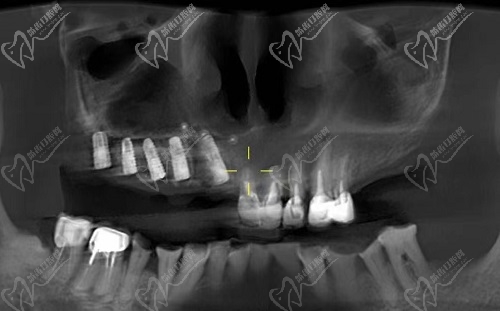

太原爱德口腔门诊部在种植牙技术上是非常强的,针对单颗/多颗种植、半口/全口种植等都有着独到的技术与见解,在种植过程中均采用的是全数字化诊疗种植技术,而且在种植牙种类品牌方面也是非常多的,每个人都可以选择适合自己的种植体。

姜娜院长会根据缺牙患者的实际情况来制定专属的种植方案,种植过程都是在3D导航下操作的,可以使每个牙齿都能准确的进行种植,而且在诊疗过程中还不会伤害到健康牙和毗邻组织,还使得种植牙更加稳固耐用,并且增加了种植牙的使用寿命,同时还是媲美真牙的,可以让大家畅快的享受美好生活。